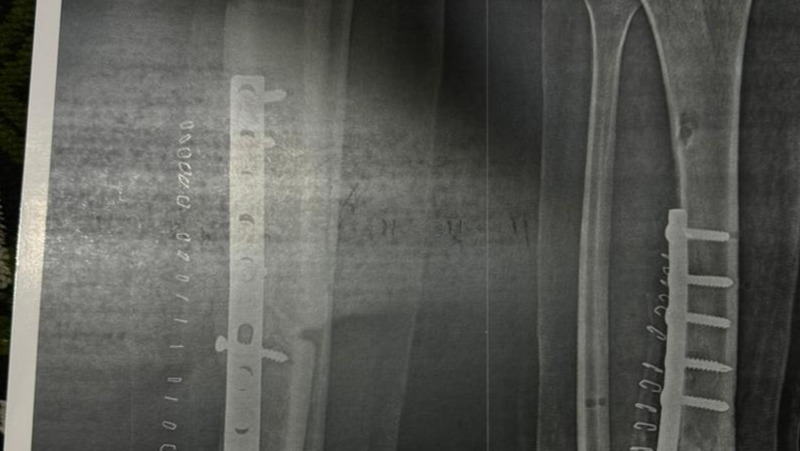

As previously mention, Khaled was admitted to the hospital suffering from a fractures of the left femur, right tibia, right 2nd, 3rd, and 4th metacarpal bones, and the proximal phalanx of left middle finger.

In addition, he has severe skin and soft tissue loss on the buttocks and left leg, and major injury to the left hand tendons and nerves. On May 14th, Khaled had the following operations:

1) Shortening and external stabilization of the left femur;

2) Direct primary repair of the sciatic nerve;

3) Skin grafts on the heel and raw areas on the left lower limb and the gluteal area and infragluteal crease (unfortunately his body rejected the last two grafts);

4) Above knee cast of his right lower limb.

From Khaled's caretaker: "Khaled is in good health. Four days ago, we visited the doctor for a check-up and had an X-ray to assess the difference in his leg length. It seems that he will need about 20 more days for both legs to become equal in length.

They also did X-rays for his thigh, and unfortunately, the healing is only 70% complete. It still needs more time, or Khaled might have to undergo surgery for a bone graft. The doctor will have to decide next week.